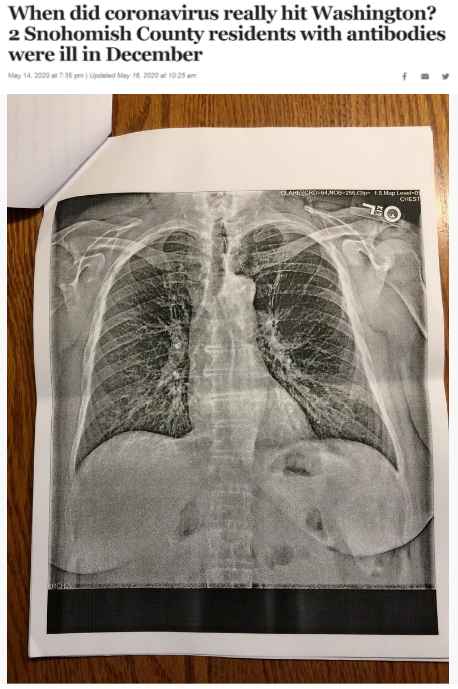

據(jù)《西雅圖時報》去年5月14日報道,華盛頓州斯諾霍米什縣的兩位居民在2019年12月出現(xiàn)類似新冠肺炎的癥狀,之后對他們的新冠病毒抗體檢測呈陽性反應(yīng)。這一結(jié)果表明,新冠病毒可能比想象中更早在當(dāng)?shù)爻霈F(xiàn)。

△《西雅圖時報》報道截圖(題圖中的X光片顯示其中一位斯諾霍米什縣居民的肺部“過度充氣”并出現(xiàn)“線性混濁”。醫(yī)生認(rèn)為,這可能是疊加上呼吸道肺部感染的表現(xiàn)。)